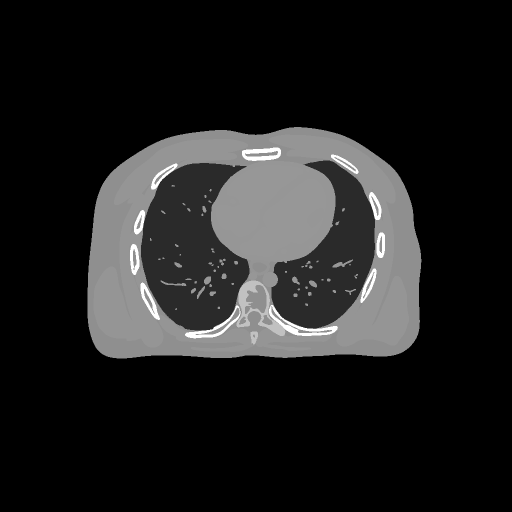

4.2 Computerized tomography reconstruction.

In this subsection we consider the computerized tomography reconstruction (CT) using TV-L2subscript๐ฟ2L_{2} model i.e.

(28) argโกminxโˆˆโ„dโ€‹โˆฅ๐’œโ€‹xโˆ’fโˆฅ22+ฮฝโ€‹โˆฅโˆ‡xโˆฅ1.๐‘ฅsuperscriptโ„๐‘‘superscriptsubscriptdelimited-โˆฅโˆฅ๐’œ๐‘ฅ๐‘“22๐œˆsubscriptdelimited-โˆฅโˆฅโˆ‡๐‘ฅ1\underset{x\in\mathbb{R}^{d}}{\arg\min}~{}\lVert\mathcal{A}x-f\rVert_{2}^{2}+\nu\lVert\nabla x\rVert_{1}.

Here x๐‘ฅx is a vectorized image i.e. an s1ร—s2subscript๐‘ 1subscript๐‘ 2s_{1}\times s_{2} 2D image is stacked into a d=s1ร—s2๐‘‘subscript๐‘ 1subscript๐‘ 2d=s_{1}\times s_{2} dimensional column vector (3D case is similar). The operator ๐’œ๐’œ\mathcal{A} is the X-ray transform, fโˆˆโ„n๐‘“superscriptโ„๐‘›f\in\mathbb{R}^{n} is the measured projections, ฮฝ>0๐œˆ0\nu>0 is a regularization parameter, and โˆ‡โˆ‡\nabla is the discrete gradient operator. The dimension of the operator ๐’œ๐’œ\mathcal{A} is generally very large, so traditionally we can use parallelization to compute the gradient of โˆฅ๐’œโ€‹xโˆ’fโˆฅ22superscriptsubscriptdelimited-โˆฅโˆฅ๐’œ๐‘ฅ๐‘“22\lVert\mathcal{A}x-f\rVert_{2}^{2} [43]. We use this example to verify if stochastic algorithms can further reduce the computation cost.

4.2.1 2D case.

The follows are the settings of the experiment in 2D:

• โ€ข

For operator ๐’œ๐’œ\mathcal{A}, we use fan beam scanning geometry [43] where the number of detectors is nโ€‹d=512๐‘›๐‘‘512nd=512, the number of viewers nโ€‹v=360๐‘›๐‘ฃ360nv=360. Thus the dimension of f๐‘“f is n=nโ€‹dโˆ—nโ€‹v=184320๐‘›๐‘›๐‘‘๐‘›๐‘ฃ184320n=nd*nv=184320.

White noise with mean 0 variance 0.1 is added to the measured projection f๐‘“f.

The proposed SVRG-PDFP algorithm is compared with PDFP [7], Stochastic PDFP (SPDFP) without SVRG [44], OPG-ADMM [32], and SVRG-ADMM [40].

The number of viewers is divided into 360nโ€‹vโ€‹b360๐‘›๐‘ฃ๐‘\frac{360}{nvb} non-overlap blocks(the number of viewers in each block is nโ€‹vโ€‹b๐‘›๐‘ฃ๐‘nvb). This yields that the batch size is b=nโ€‹vโ€‹bโˆ—nโ€‹d๐‘๐‘›๐‘ฃ๐‘๐‘›๐‘‘b=nvb*nd. We choose nโ€‹vโ€‹b=20๐‘›๐‘ฃ๐‘20nvb=20 for OPG-ADMM, SPDFP and SCAS-ADMM and nโ€‹vโ€‹b=15๐‘›๐‘ฃ๐‘15nvb=15 for both SVRG-ADMM and SVRG-PDFP.

All the algorithms are terminated when they reach the maximum epoch number(effective pass).

The experiment is performed on two different devices: NVIDIA GeForce GTX 1050 Ti GPU with 768 Cuda cores and TITAN RTX GPU with 4608 cores. The version of Matlab is 2018b. The comparisons of different algorithms on different devices will be reported.

Refer to caption

(a) PSNR (TITAN RTX)

(b) PSNR (GTX 1050 Ti)

Figure 3: Different method for reconstructing image over 10 repetitions.

(a) PSNR = 30

(b) PSNR = 35

(c) PSNR = 37

(d) PSNR = 43

Figure 4: Different method for reconstructing image over 10 repetitions.

(a) Ground truth

(b) PDFP, PSNR= 44.94

(c) SPDFP, PSNR= 37.29

(d) SVRG-PDFP, PSNR= 44.98

(e) OPG-ADMM, PSNR= 37.45

(f) SVRG-ADMM, PSNR= 43.82

Figure 5: Reconstructed image (averaged) with different methods over 10 repetitions.

FIG 3 give the results of the peak signal-to-noise ratio (PSNR) of the reconstructed images over time on two devices. It can be seen that stochastic algorithms without SVRG can not get high PSNR comapred to that with SVRG and the full batch PDFP. The performance of SVRG-PDFP is as good as PDPF with the device TITAN RTX while SVRG-PDFP behaves the best with the devices with less cores. FIG 4 record the computational time of different algorithms when PSNRs reach 30,35,37,433035374330,35,37,43 on the two different devices. We can see that when the computational resource is powerful (with many parallel cores), the full-batch PDFP can be highly parallized and the stochastic algorithm does not gain in general. However, when the cores number is not very high, stochastic algorithms with SVRG are beneficial compared to deterministic algorithms. FIG 5 gives the reconstructed images with different algorithms and we can see that the one with SVRG-PDFP achieves the highest PSNR as the full batch PDFP.